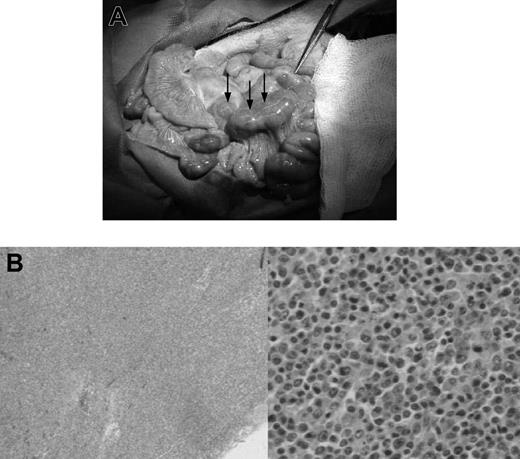

In animals with lymphoma or PTLD, mild hepatosplenomegaly and diffuse lymphadenopathy that included prominent enlargement of mesenteric lymph node chain were observed at autopsy (Figure 1A). This lymphadenopathy, in some cases, also included significantly enlarged lymph nodes in the neck and inguinal regions of the animal. Lymphoid tissues had histologic evidence of atypical cells and destruction of normal architecture (Figure 1B). Animals with leukemia had less significant lymphadenopathy and greater hepatosplenomegaly, with firmer and paler organs (Figure 2A). Lesions 0.5 to 1 cm in diameter were commonly found on the liver of animals with leukemia. Pleural effusions and ascites were not uncommon in these animals. There was also histologic evidence of diffuse infiltration consisting of large, pleiomorphic malignant cells containing heterochromatic nuclei. These cells were present throughout all vascularized tissues such as the kidney and the lung, and they were also prominent in the bone marrow (Figure 2B).

Gross pathologic and histologic findings of lymphoma (PTLD) in miniature swine. (A) Animals that developed lymphomas or PTLD typically had pronounced lymphadenopathy, as represented by animal 17018. Image was acquired using a Kodak camera (Eastman Kodak, Rochester, NY) model Easyshare Z740 with a 45.5-mm to 55-mm lens adapter. No further image processing was done. (B) Lymph node tissue harvested from these animals demonstrated destruction of normal architecture and predominance of abnormal cells as represented by animal 13271. Slides were viewed with an Olympus BX51 compound microscope (Olympus America, Melville, NY) of sections stained with hematoxylin and eosin (H&E; Hematoxylin Gill's Formulation no. 2, Fisher Diagnostics, Fair Lawn, NJ; Eosin-Y, Richard-Allan Scientific, Kalamazoo, MI) using a lens at 40× (left) and 400× (right). Images were acquired using an Olympus digital microscope camera (Olympus America) model Q-Color 3, and were processed with Adobe Photoshop CS version 8 software (Adobe Systems, San Jose, CA).